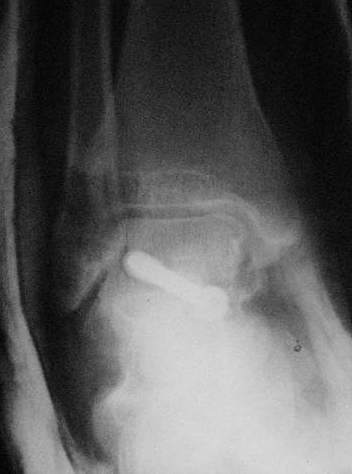

Прооперировали таранную кость, доступ внутренний без пересечения внутренней лодыжки. Хотя покаялись, что не пошли на остеотомию лодыжки внутренней. Винт

провели через небольшой передний доступ.